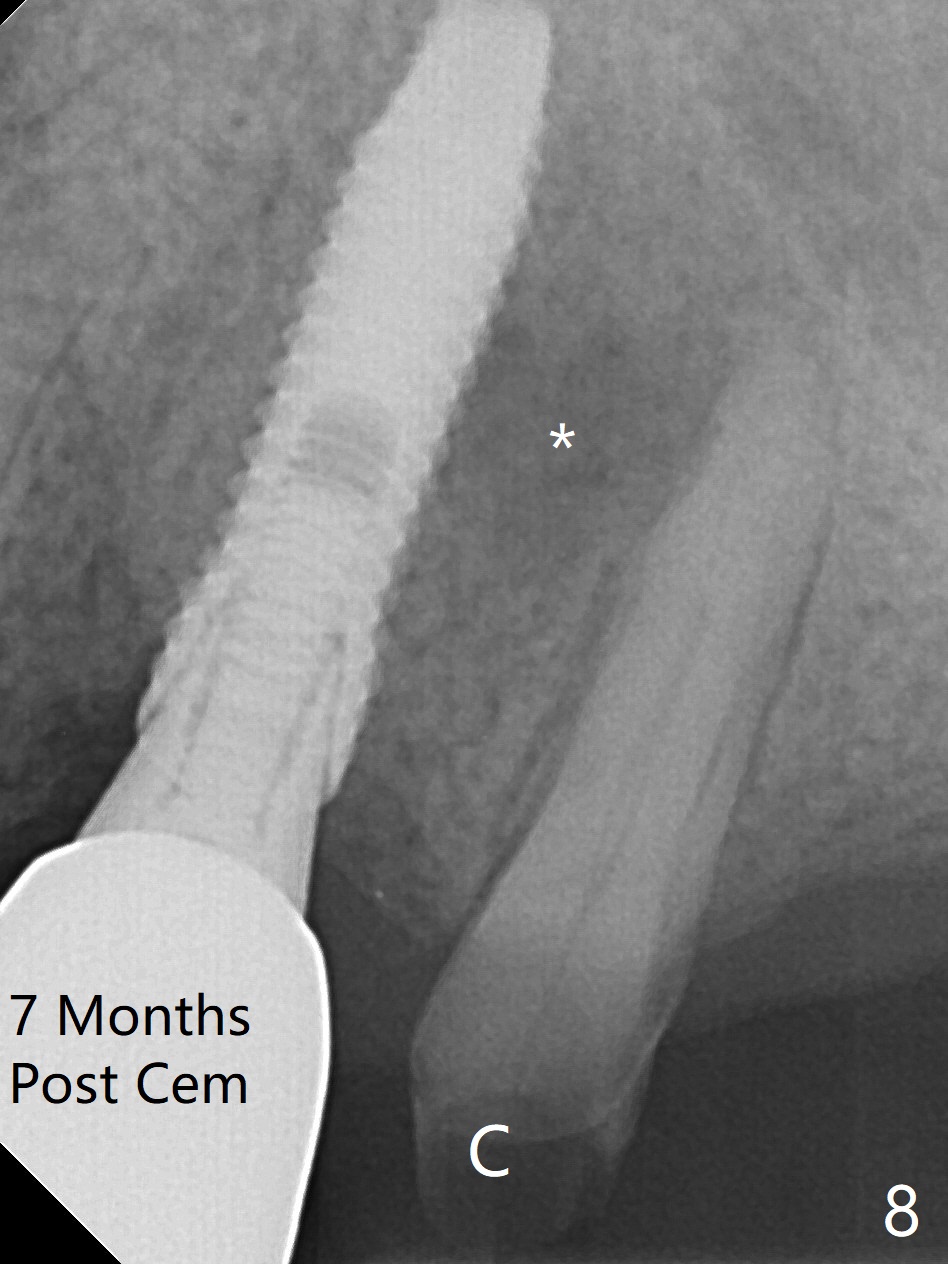

After extraction of the oval-shaped residual roots at #12 (Fig.1), osteotomy is initiated in the palatal socket for 18 mm; since the root of the canine curves distal (Fig.2 red dashed line), the osteotomy cannot afford to move mesial and extend more apical. A 3.8x15 mm implant is placed with > 50 Ncm (Fig.3). With immediate placement of a 4.5x4(3) mm abutment, an immediate provisional is fabricated to close the sockets (Fig.4 P). The provisional has clearance from the RPD clasps (Fig.5). In fact the implant could be longer, as shown by immediately postop panoramic X-ray (Fig.6). The implant seems to be osteointegrated 3 months postop (Fig.7). The tooth #13 is symptomatic with caries (Fig.8 C) 7 months post #12 crown cementation; the #13-15 FPD dislodges. The upper left quadrant is cold and hot sensitive 2.5 months post RCT (Fig.9); although there is mild percussion at #13, pulpal test shows that the tooth #15 has lingering pain. The FPD was recemented temporarily after RCT; it cannot be removed. The implant crown has been loose for several months during the pandemic before he returns 2 years 7 months post cementation. In fact the abutment has been not seated completely (from Fig.3 to 9). The crown/abutment is removed from the mouth; the crown is sectioned and separated from the abutment; the latter is reseated, but incompletely (Fig.10 <). With suspicion of the mesial crestal contact, profile drills 4.6 and 5.5 mm are used without effect. A new (old probably being worn) and longer (easy to turn in the narrow space) abutment is finally seated completely (Fig.11 (no gap)). After occlusal adjustment, abutment level impression is taken for a new crown.